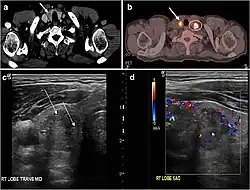

Fig. 8. A 48-year-old male patient post total thyroidectomy with PTC recurrence. a Transverse greyscale ultrasound of the neck demonstrates a left thyroid bed heterogeneous, predominantly hypoechoic irregular lesion with calcifications (white arrow). b A spot image of iodine 123 total body scan of the neck demonstrate a focus of abnormal radiotracer uptake at the left thyroid bed (Black arrows) between the annotated markers. c Enhanced axial CT scan of the neck demonstrates an enhancing large left thyroid bed mass (white arrow) with no calcifications. The lesion exerts a mass effect on the oesophagus (black arrow) and is inseparable from the trachea.[1] -

Fig. 9. A 58-year-old male patient with persistence PTC at thyroid bed with hypervascular nodal metastasis. a–c Transverse greyscale and colour Doppler neck ultrasound demonstrate hypoehoic soft tissue in the left thyroid bed (white arrow in a). There are a heterogeneous enlarged lymph nodes at level 2 and 3 with markedly increased vascularity (white arrow in b and c). d–f Enhanced axial CT images of the neck demonstrate a 2.7 × 1.4 cm hypodense soft tissue lesion anterior to the left carotid sheath (white arrow). There are left-sided enhancing abnormal and enlarged lymph nodes at cervical level 2 and 3 (black arrows).[1]